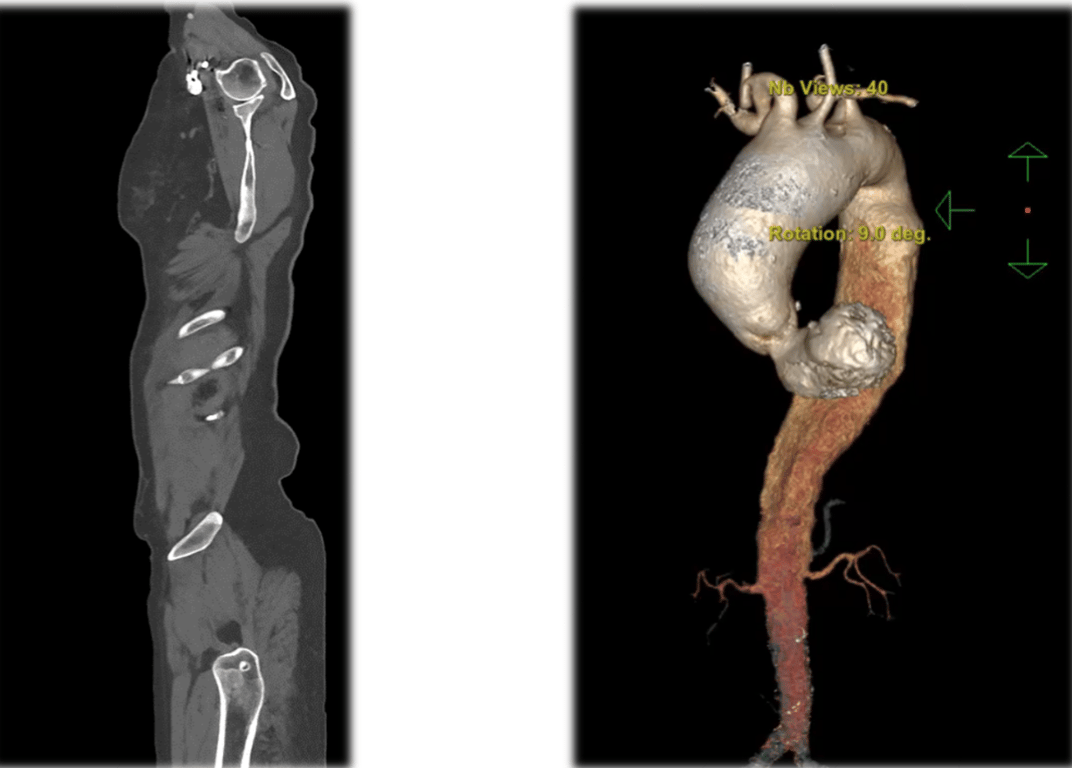

"Аорта — це велика магістральна судина, яка розповсюджує кров із серця по всьому організму. В цієї пацієнтки була уражена аорта на всьому протязі: від аортального клапана до клубових артерій. Це було дуже непросте рішення, тому ще комплексна патологія, і наша задача була зробити так, щоб вона була здоровою", — розповів заступник директора з хігургічної роботи Сергій Варбанець.

Аорта. Фото: пресслужба

За його словами, діаметр аневризми в цієї пацієнтки був майже 7 сантиметрів. Такий діаметр має шанси розриву упродовж року. Варбанець зазначив, що у 30% пацієнтів вся аорта може розірватися і лопнути. Що стосується пацієнтки, то у перспективі року або двох шансів повноцінно жити у неї не було.

Аневризма у пацієнтки. Фото: пресслужба

Першою пацієнткою в Україні, яка перенесла таке важке хірургічне втручання стала 76-річна Віра Сандул. Лікарі поміняли їй аортальний клапан, висхідну аорту, дугу аорти, низхідну грудну аорту та черевну аорту.